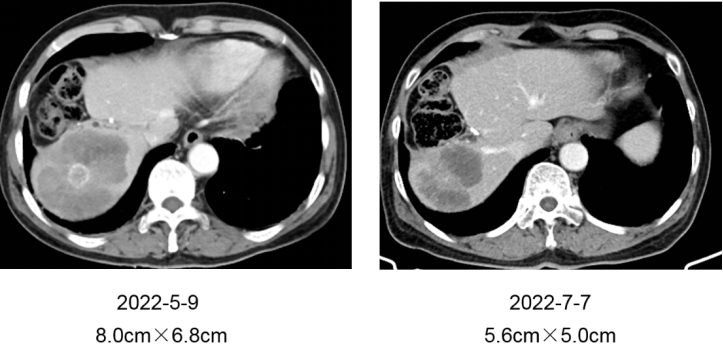

再次调整治疗方案,于2022-5-12 使用贝伐珠单抗+TAS-102方案(2周方案),2022-7-7 评估:肝脏病灶缩小至5.6cm×5.0cm,疗效PR(图四)。治疗期间患者自觉反应轻,耐受性较好。

△图四